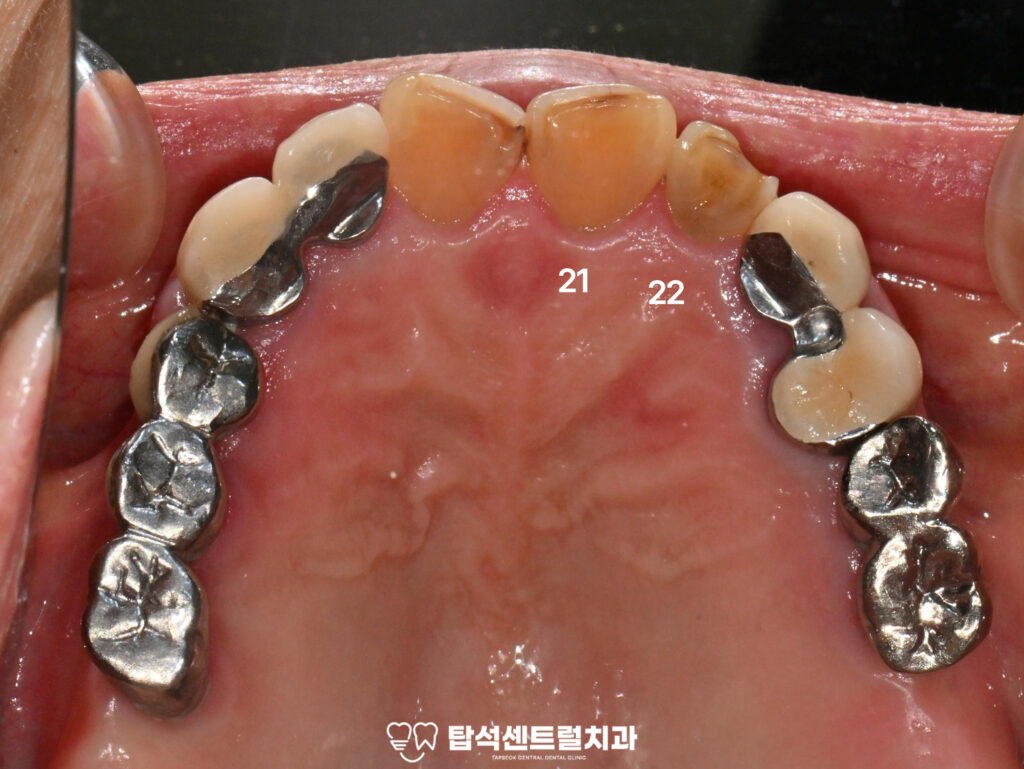

- 상악 좌측 전치부 치근 우식

의정부 치과 에서 준비한 구강 내 사진을 살펴보면

상악 좌측 전치부인 21, 22번 치경부를 중심으로

치근면까지 깊은 우식이 관찰됩니다.

특히 이번 증례에서는 치은연을 따라

우식이 치근 방향으로 진행되며

와동의 깊이 또한 상당한 상태였습니다.